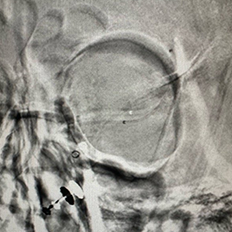

One of the key components of our stroke center is the Neuroangiography biplane suite. This advanced imaging system enables precise diagnosis and treatment of stroke and brain aneurysms. However, the cost of this technology is substantial, with a single biplane suite costing millions of dollars. Your support will directly contribute to acquiring this life-saving technology and ensuring better stroke treatment for thousands.

Equip local doctors with the skills need to perform critical procedures, such as mechanical thrombectomy for ischemic stroke and aneurysm coiling for subarachnoid hemorrhage

We provide devices and treatment of complex brain aneurysms and vascular malformations free of cost. These are some of the complex brain aneurysm we have recently treated in Pakistan. Devices and catheters used for all procedures were provided by Pakistan Stroke Initiative, and in some cases charges for hospitalization as well.

Although we typically don’t take photos of our patients and their families, many of those we have treated have made special requests for it. Visiting physicians from abroad have consistently been impressed by the gratitude and appreciation shown by our patients and their families for the care they receive.

All of these photos have been shared with the permission of the patients and their families.